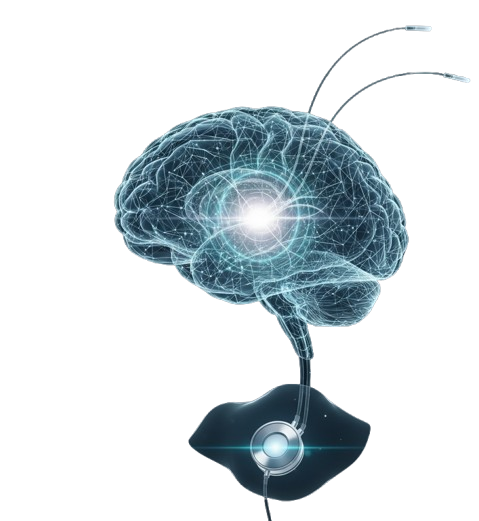

Beynin hedeflenen bölgelerine ince elektrotlar yerleştirilir ve bu elektrotlar cilt altına yerleştirilen küçük bir uyarı cihazına bağlanır. Uyarı ayarları hekimler tarafından yapılır ve takip süreçlerinde düzenlenebilir.

Beynin belirli bölgelerine yerleştirilen elektrotlar ile elektriksel uyarı verilmesini sağlayan cerrahi bir tedavi yöntemidir. Özellikle Parkinson hastalığı, distoni ve esansiyel tremor gibi hareket bozukluklarında kullanılabilir. Uygunluğa hastanın hekimi tarafından karar verilir.

Beyin Pili ile Yaşam Kalitesi